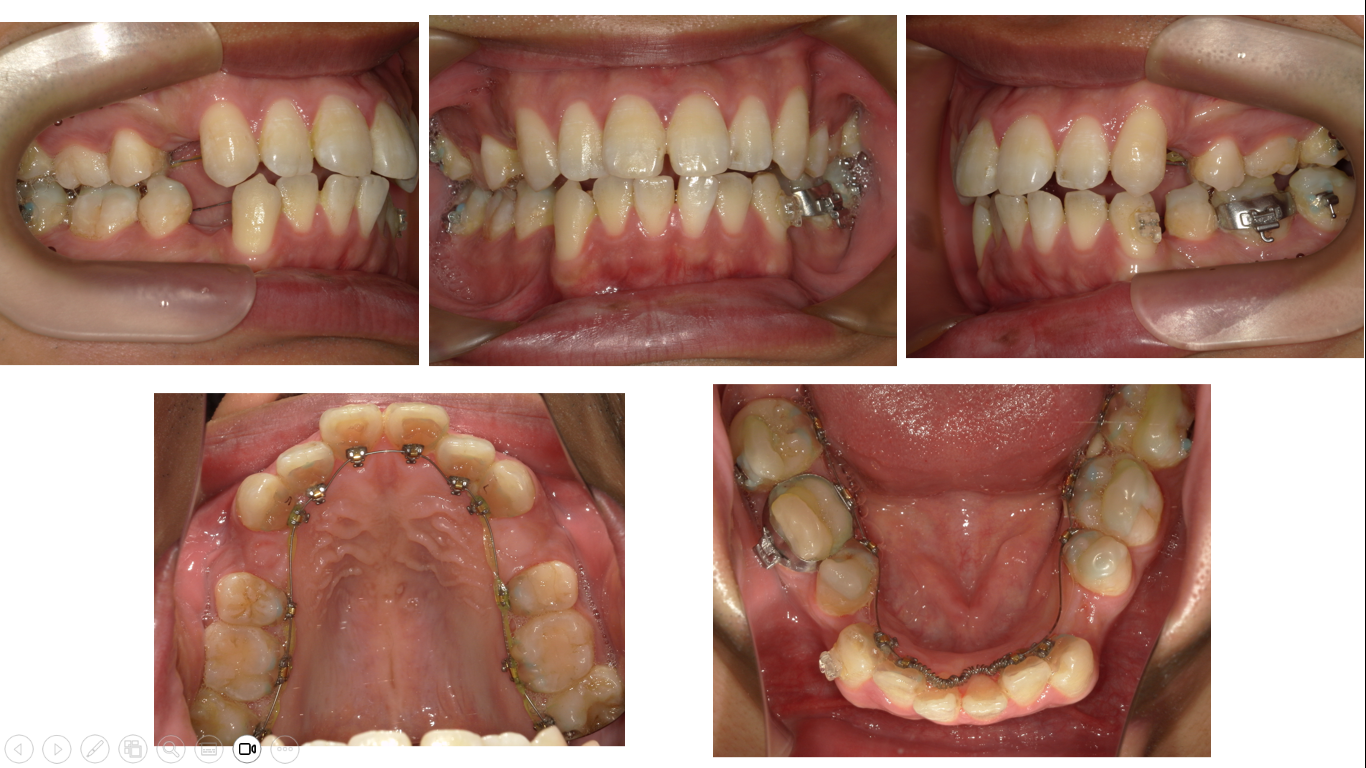

矯正症例 140 AngleⅠ級上下顎前突、舌側矯正,口ゴボ,裏側矯正

治療開始年齢29歳3か月、治療期間3年3か月、抜歯部位:上下顎左右4番、下顎左右8番、上顎右側8番、治療費総額¥1,580,000(税込み)

口蓋正中部にアンカースクリュー除去の跡があることでわかる通り、この症例では口蓋に装置を装着しています。舌側矯正ではどうしても上顎前歯部にトルクを加えるのが難しいので今まで他の症例で様々な方法を試した上で、口蓋側の装置に落ち着きました。誤解されないように説明を加えるます。試すと言っても、それは厚労省から認可されている材料、機器を用いていますし、適切な適用をしています。実験をしているのではありません。今回の症例では薬事法認可のビートルの名称がある口蓋の装置を用いました。